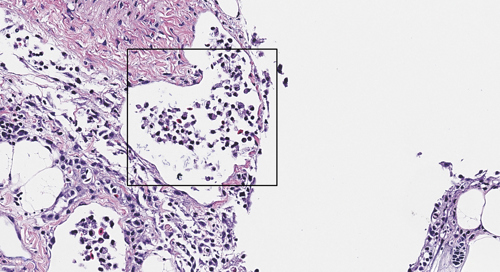

Bilde 1: Histologisk snitt. HE-farging. Betennelse i øye med bakterier, fra en sak med påvist Pseudomonas spp.

Pseudomonas spp. er vanlig forekommende bakterier, og de fleste infeksjoner blir oppfattet som opportunistiske infeksjoner som et resultat av dårlig vannkvalitet. I noen tilfeller kan imidlertid Pseudomonas fluorescens være hovedproblemet til økt dødelighet i settefiskanlegg. Gjennom vinteren har vi imidlertid sett flere tilfeller fra PO7 og 8 av hittil ukjente varianter av bakterien som har gitt systemisk infeksjon, og forårsaket dødelighet hos affisert laks i sjø.

Sykdomstegn hos laks med infeksjon med Pseudomonas spp. har vært utstående øyne, blødninger i øyne og svømmeblære, væske i hjertehule, fibrin på lever og lesjoner ved brystfinnebasis. Det har vært økt dødelighet forbundet med sykdomsutbruddene. Sykdommen har blitt håndtert med å ta ut enkeltmerder, samtidig som fiskegruppene i størst mulig grad har fått stå i ro. I tilfeller hvor det har vært behov for behandling, har det blitt valgt mest mulig skånsomme metoder.

Bakterieisolater fra utbruddene har blitt analysert med utvidet sekvensering, hvor flere gener har blitt undersøkt. Resultatene viser at isolatene fra PO7 er identiske med hverandre, men ikke like de som er blitt påvist fra PO8. Vi overvåker alle innsendelser hvor det er mistanke om Pseudomonas spp. for å følge situasjonen videre.